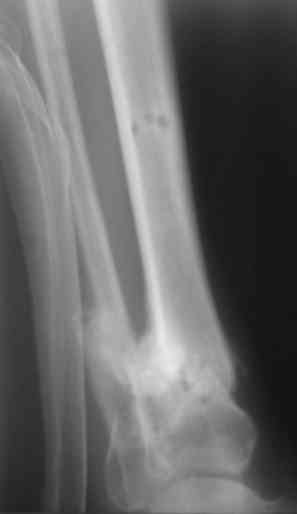

Есть у меня результат такого метода. Тема обсуждалась. Как говорится - лечили всем форумом. Рана, правда, не огнестрельная - OFFтопик.

Больной случайно попал в поле зрения с переломом шейки бедра. Страдает хр. алкоголизмом. От когда-то предложенного удлиннения голени пациент отказался. После снятия аппарата он пропал как с белых яблонь дым ...

Укорочение конечности 3 см. Передвигался без дополнительной опоры с "нарощенной" подошвой на правой обуви. Ограничение тыльного и подошвенного сгибания - умеренные (всего примерно 50%, не измерял).